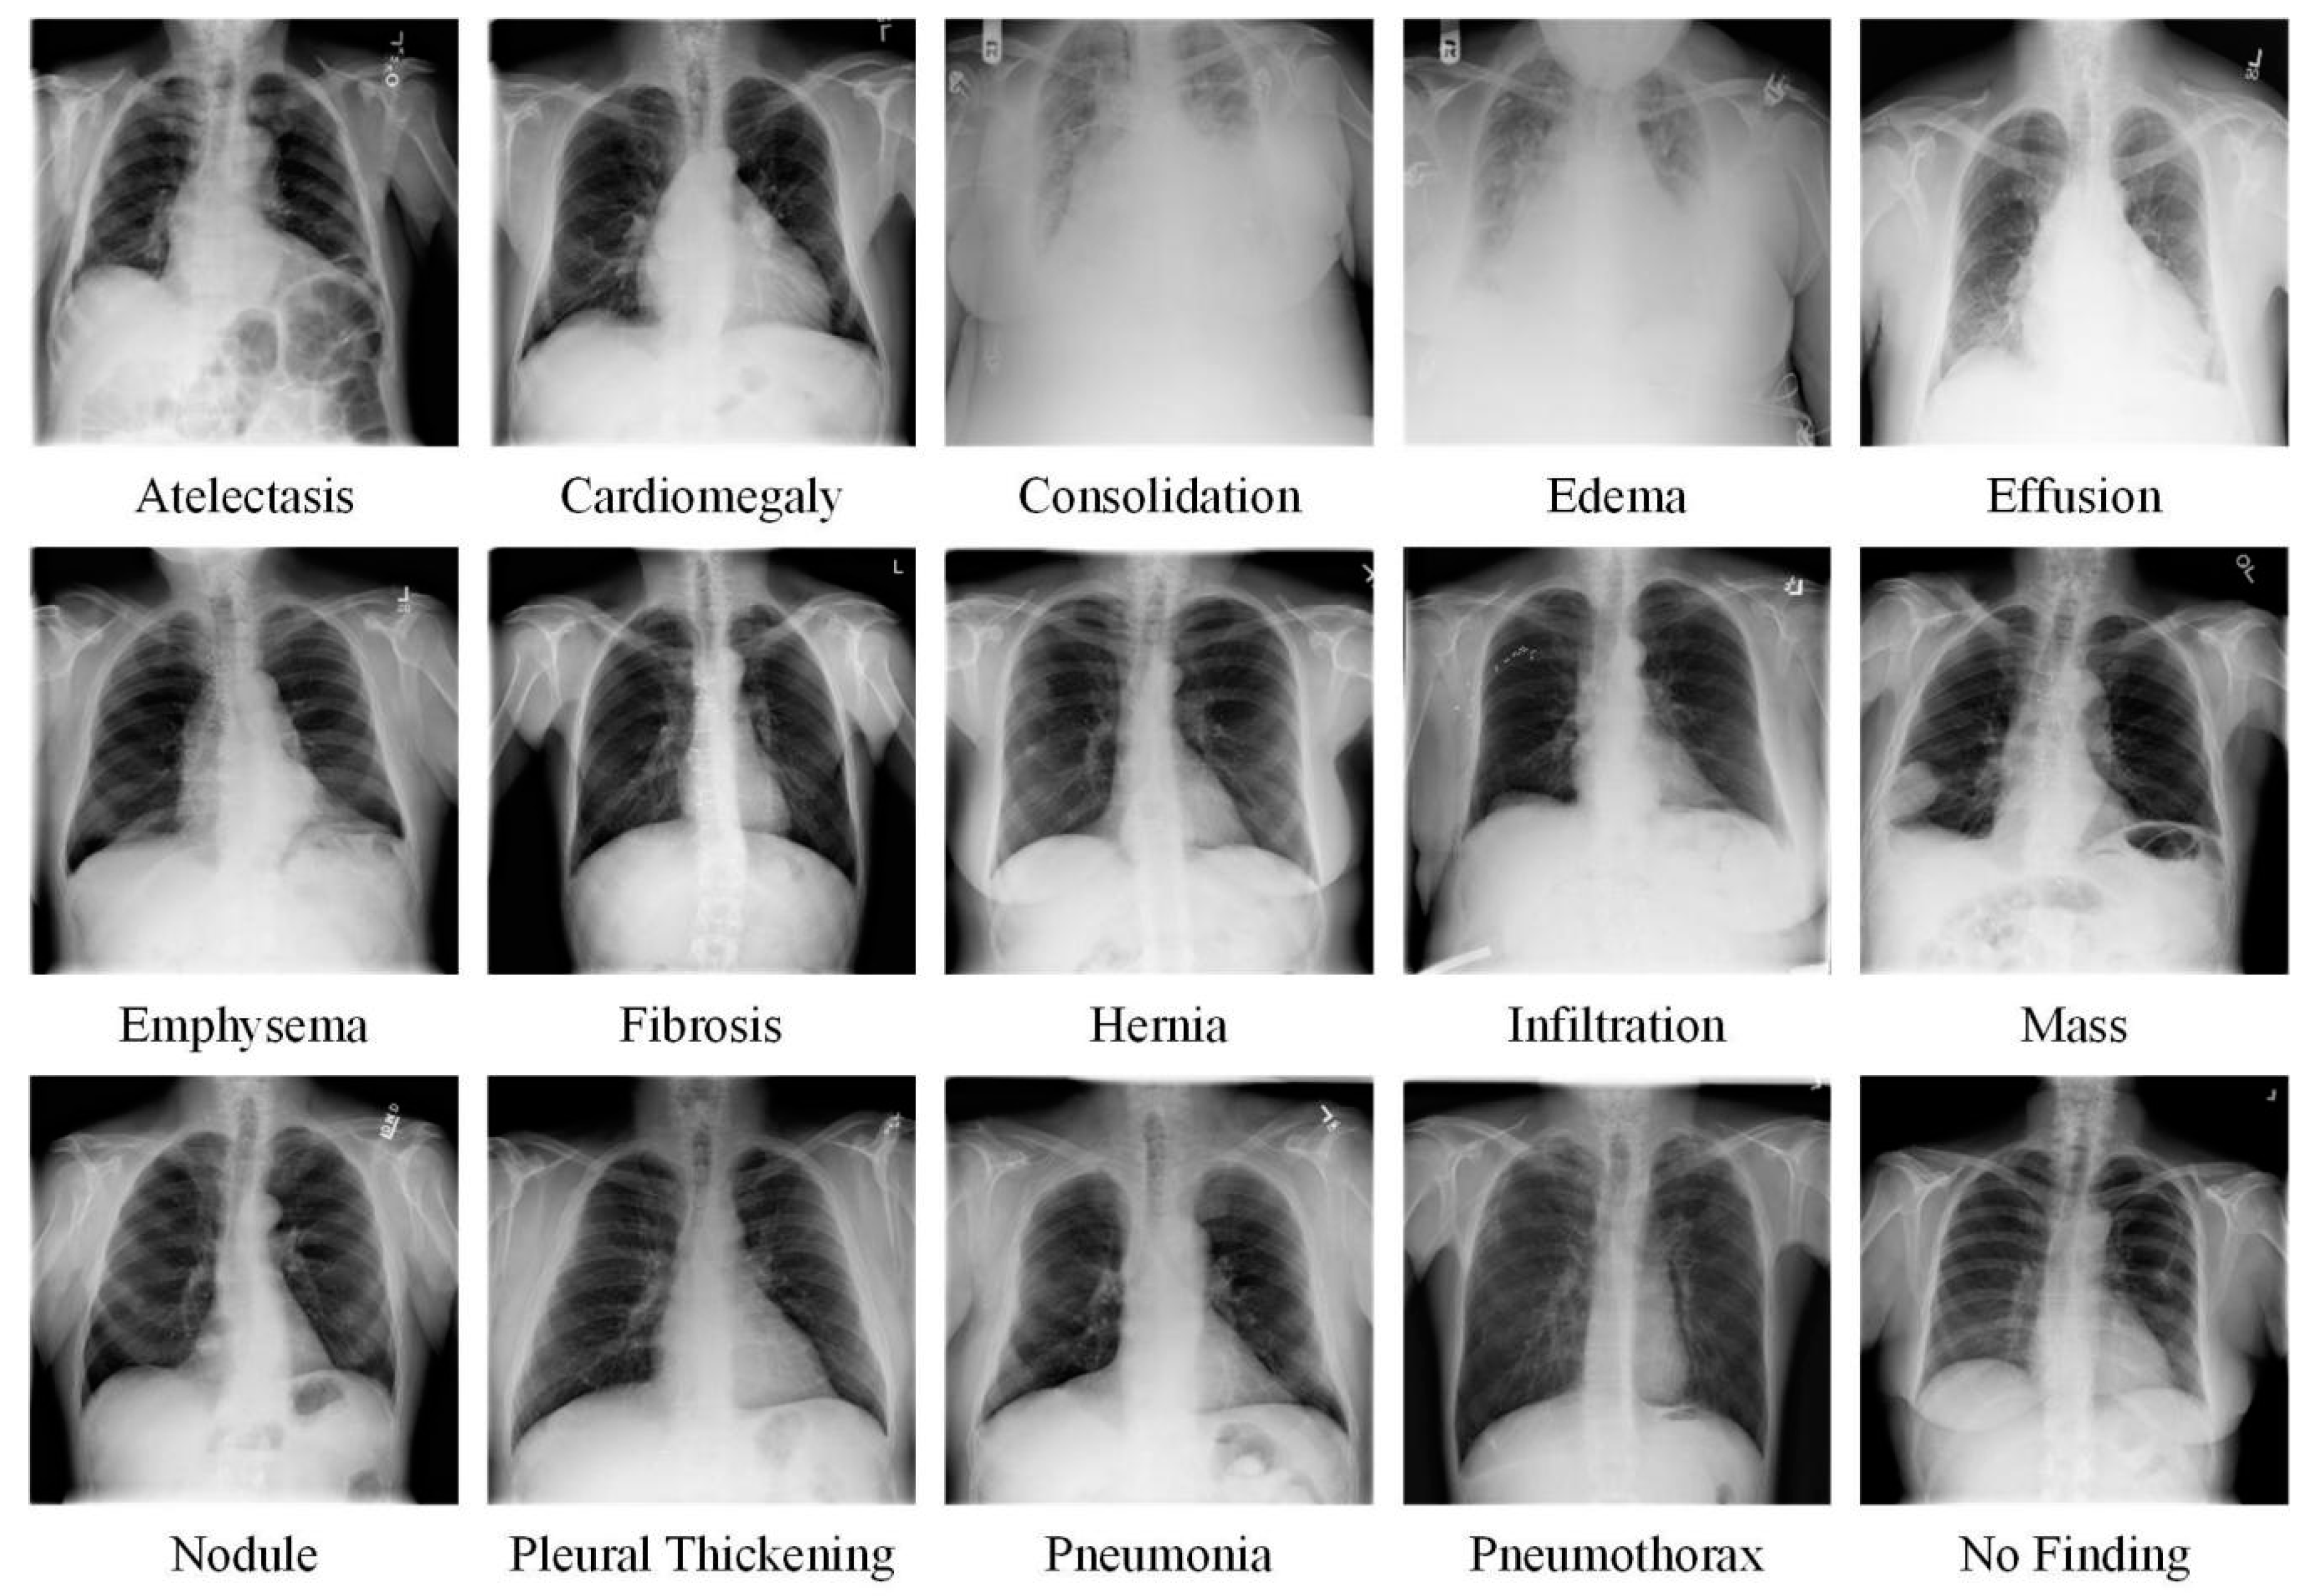

2.1. Dataset